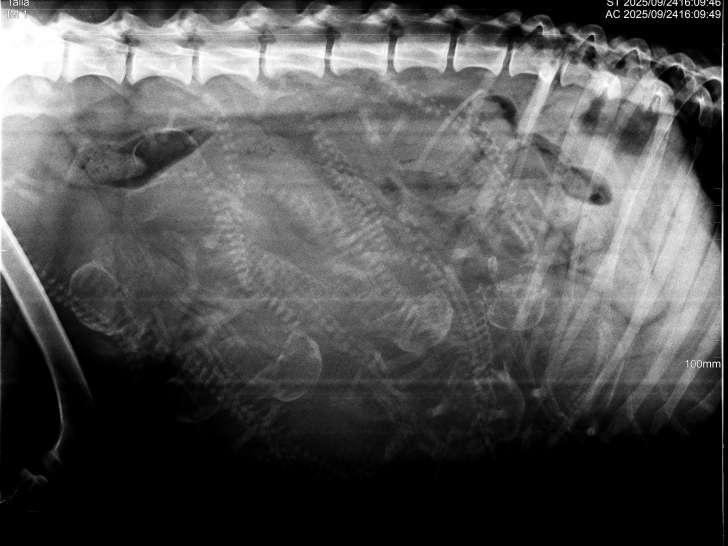

Nous avons la joie d’annoncer l’arrivée prochaine de chiots Rhodesian Ridgeback LOF, issus de l’union soigneusement choisie entre Talia Hell's Rhodesian et Tyson des Carpates, tous les 2 inscrits au LOF et indemnes de dysplasie. Les tests génomiques et les radios des hanches, des coudes et des épaules ont été faits (RAS).